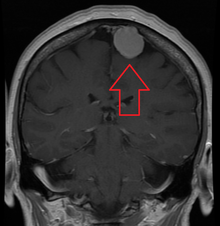

A meningioma that previously had been operated on, with surrounding edema

MRI image of a meningioma with contrast

Meningiomas are visualized readily with contrast CT, MRI with gadolinium,[14] and arteriography, all attributed to the fact that meningiomas are extra-axial and vascularized. CSF protein usually is elevated if lumbar puncture is attempted.